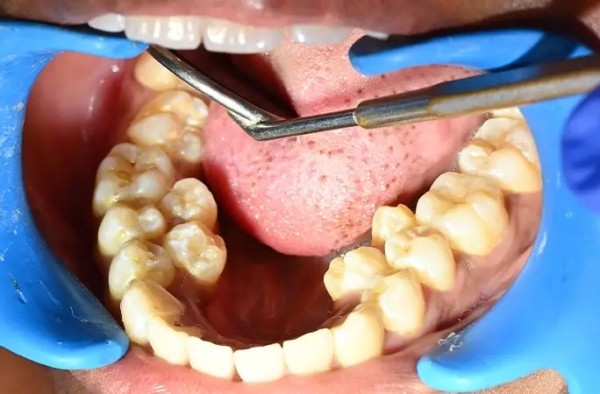

У девушки из Индии рекордное число зубов

У девушки на шесть зубов больше, чем у большинства людей: у жительницы Индии насчитали 38 зубов вместо 32-ух. При этом у неё нашли ещё два зуба, которые не прорезались. Больше только у мужчины из Канады — 41 штука.